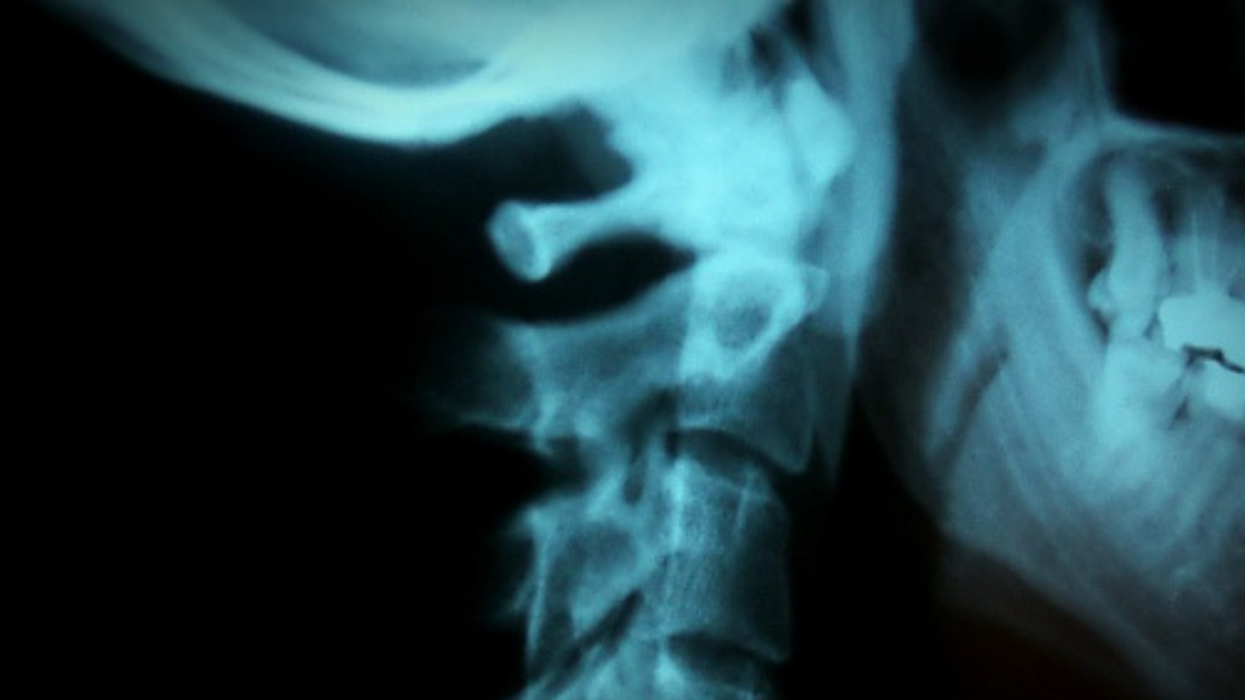

Josh Hader, a 28-year old-man, found this out the hard way. He cracked his neck and suffered from a major stroke.

He ended up at Mercy Hospital in Oklahoma City, Oklahoma. He tore his vertebral artery which leads to the brain.

Dr. Nurra Orra, a family medicine physician explained that having your neck cracked or "manipulated" can carry a risk of stroke as it risks tearing arteries.

"[It] places the vertebral artery in a precarious position prone for injury, Studies have shown a correlation between increased risk of stroke and people who get their necks manipulated."

"a tear in the lining of the artery caused an obstruction of blood flow to the brain."